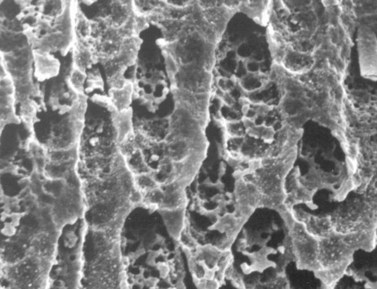

Fig. 10.30 Scanning electron microscopy image of carious dentin lining a pulp chamber that contains necrotic pulp. Many areas have localized loss of integrity of intertubular dentin (arrows).

(Reproduced from Dacre et al55 with permission of The Veterinary Journal.)